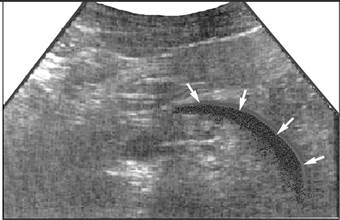

При остром панкреатите достаточно частым сопутствующим процессом является полисерозит, который эхографически выявляется в виде скопления жидкости в серозных областях – брюшной и плевральной. Количество выпота может варьировать от нескольких миллилитров до литров. В брюшной полости выпот определяется как плащевидные, эхонегативные, мигрирующие участки различной толщины и конфигурации. Наиболее частые места выявления – в сальниковой сумке, малом тазу, латеральных карманах брюшной полости, поддиаф-рагмальных областях справа и слева. Сальниковая сумка располагается сразу кпереди от поджелудочной железы. В этой области при острых панкреатитах часто наблюдается гипо- или анэхогенная полоска различной толщины (в зависимости от количества выпота), огибающая контур передней поверхности поджелудочной железы (рис. 11).

Рис. 11. Один из вариантов изображения умеренного количества жидкости в сальниковой сумке кпереди от поджелудочной железы при остром панкреатите.